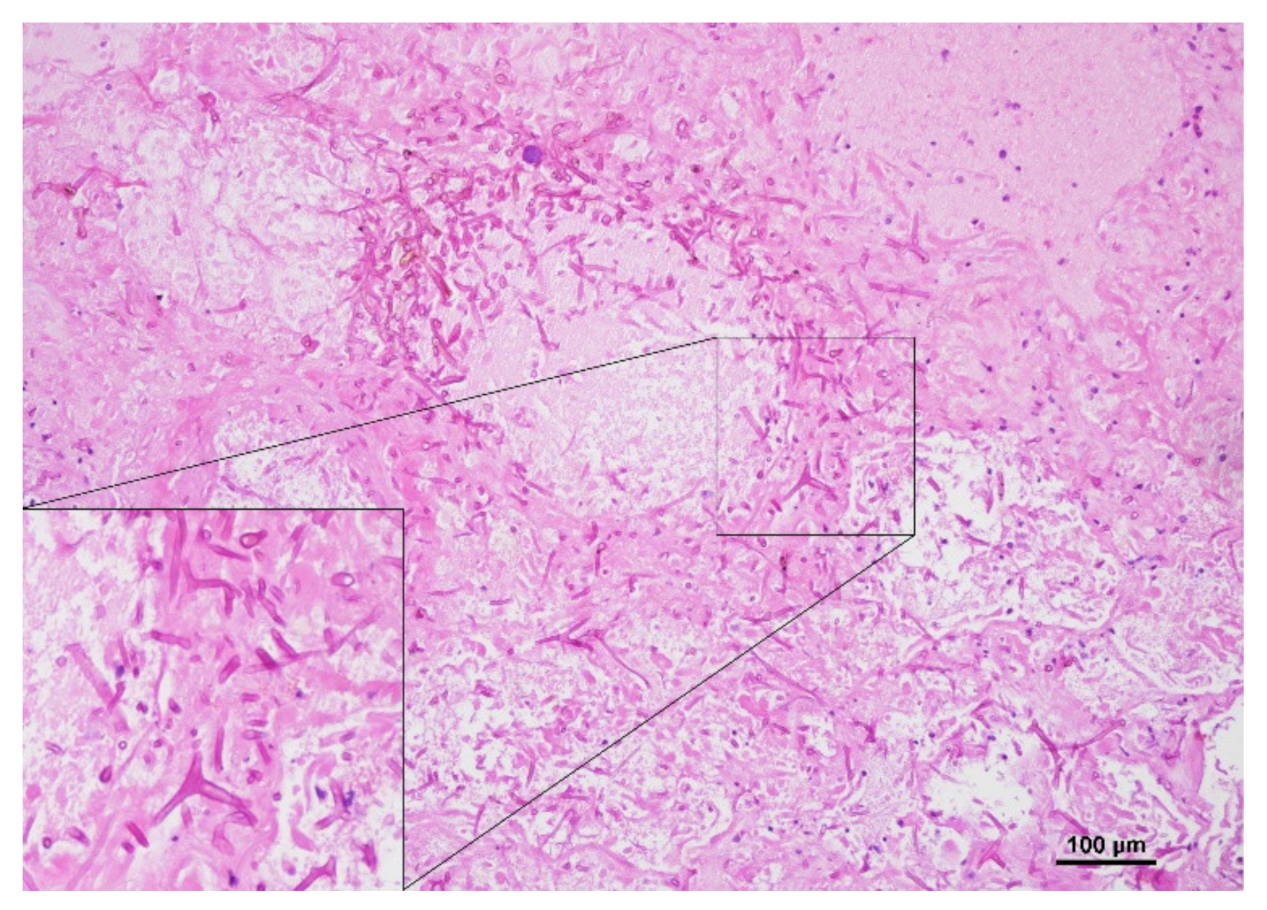

2. Case Report